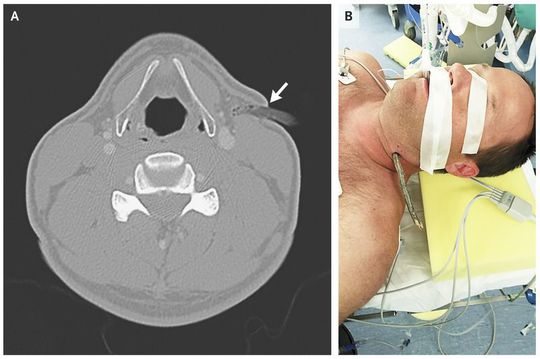

A previously well 40-year-old man was riding a mountain bike off-road when he fell and impaled his neck on a branch that was 2 cm in diameter. The patient did not attempt to remove the branch, and he transported himself to our emergency department. A computed tomographic angiogram showed the foreign body in the soft tissues of the left side of the neck at the level of the superior thyroid cartilage, extending through the platysma muscle, to the anterior margin of the sternocleidomastoid muscle (Panel A, arrow). The branch extended approximately 1.6 cm deep into the neck from the skin surface, with no evidence of vascular or airway injury (Panel A). Penetrating neck injuries can be associated with vascular, airway, cervical spine, or nerve injuries. The foreign body may be providing tamponade if a major vascular structure is injured; hence, there is a possible benefit to leaving the foreign body in place until radiologic and surgical evaluations are performed. In the operating room, the foreign body (Panel B) was removed, and the wound was explored, irrigated, and closed. The patient had an uneventful postoperative course.